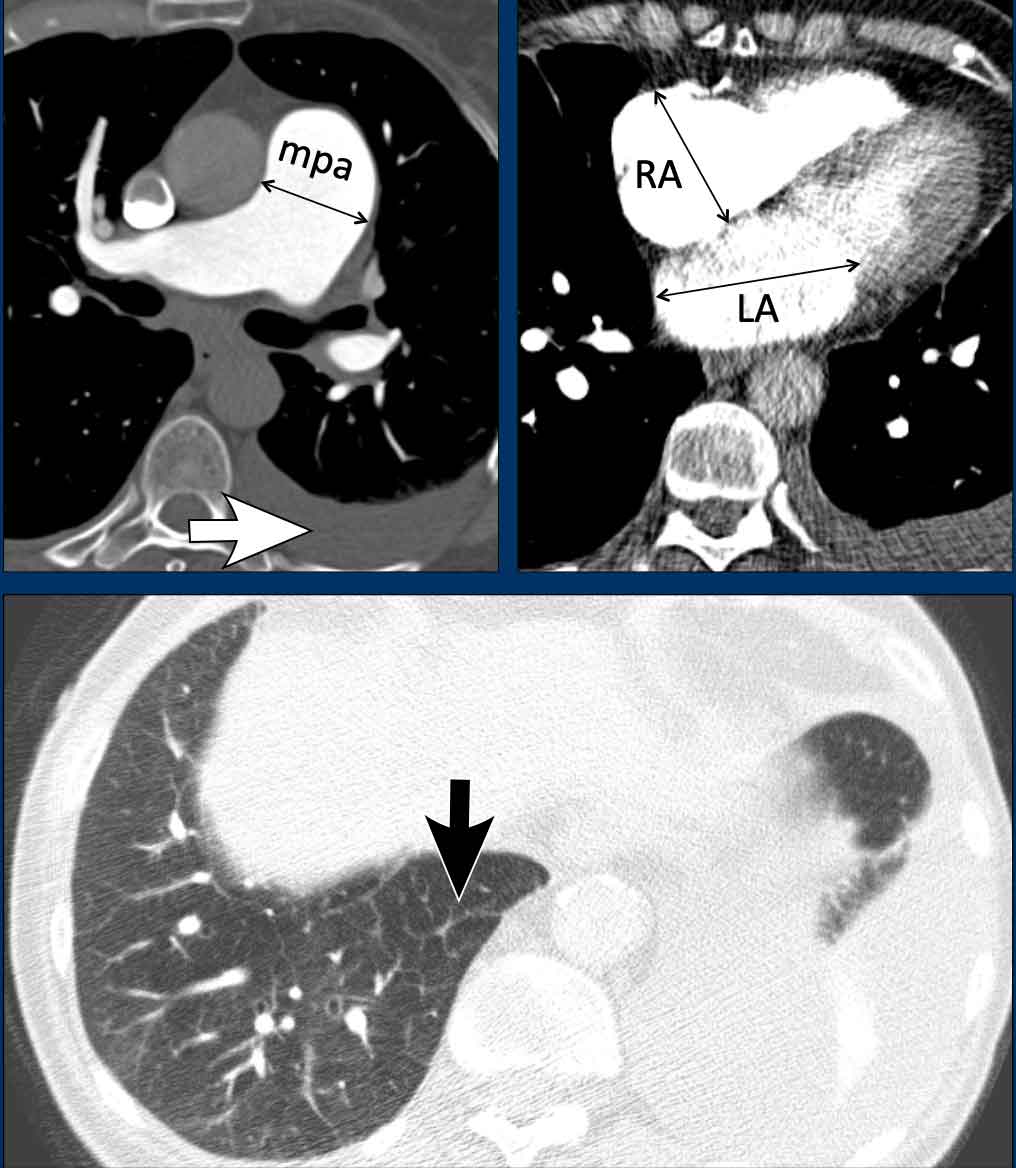

Images

In this patient with left heart disease the findings are:

1. Dilatation of the main pulmonary artery.

2. Dilatation of the right atrium and mild thickening of the myocardium of the right ventricle.

3. Dilatation of the left atrium

4. Pleural fluid (white arrow).

5. Smooth interlobular thickening (black arrow).